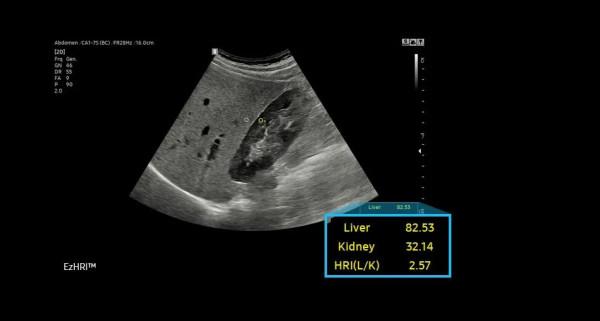

RS85 Prestige搭載了多款智慧應用,幫助臨床醫護人員做出更可靠的評估。如能夠提供HRI比率的EzHRI系統;S-Detect for Breast系統則能夠為乳腺超聲檢查提供標準化報告,並最佳化工作流;利用定量組織衰減測量來評估脂肪變性肝臟變化的TAI系統等。